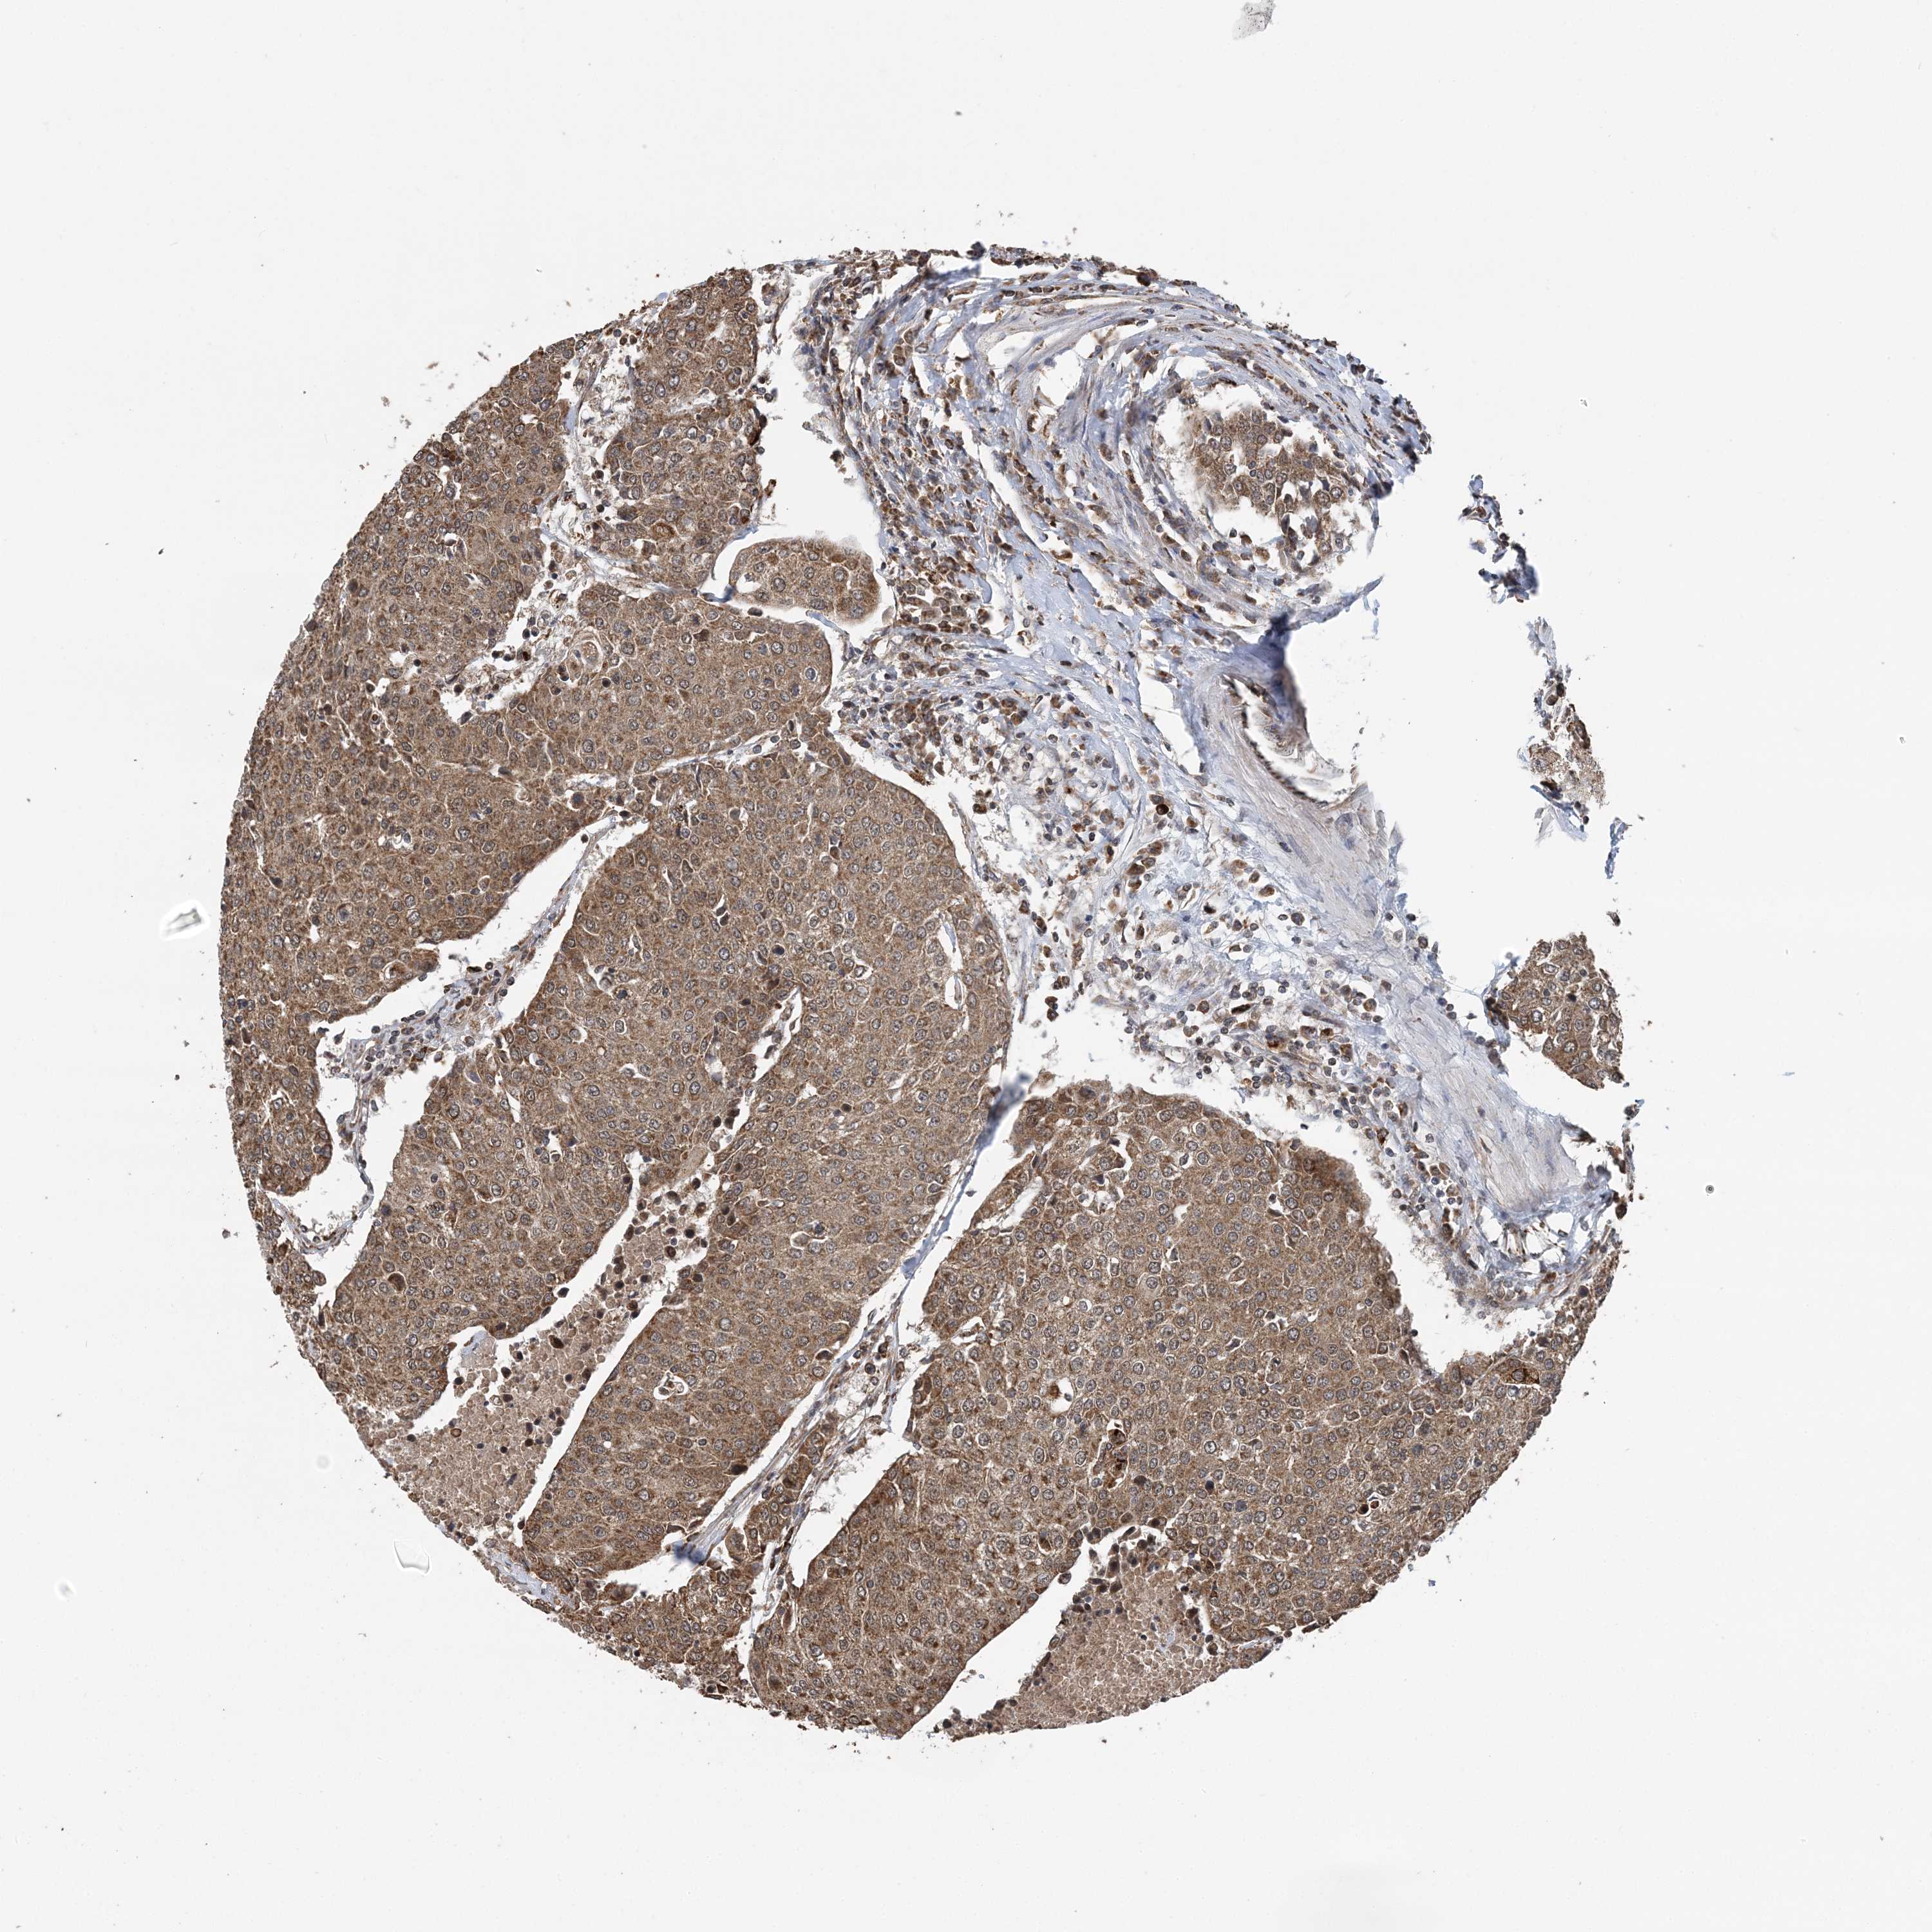

UROTHELIAL CANCER - Protein expressioni

A mouse-over function shows sample information and annotation data. Click on an image to view it in a full screen mode. Samples can be filtered based on level of antibody staining by selecting one or several of the following categories: high, medium, low and not detected. The assay and annotation is described here.

Note that samples used for immunohistochemistry by the Human Protein Atlas do not correspond to samples in the TCGA dataset.

Antibody stainingi

Antibody staining in the annotated cell types in the current human tissue is reported as not detected, low, medium, or high, based on conventional immunohistochemistry profiling in selected tissues. This score is based on the combination of the staining intensity and fraction of stained cells.

Each image is clickable and will lead to virtual microscopy that enables deeper exploration of all samples and also displays staining intensity scores, fraction scores and subcellular localization as well as patient and tissue information for each sample.

Antibody CAB037113

Staining

High

Medium

Low

Not detected

Intensity

Strong

Moderate

Weak

Negative

Quantity

>75%

75%-25%

<25%

None

Location

Nuclear

Cytoplasmic/membranous

Cytoplasmic/membranous,nuclear

Urothelial carcinoma, Low grade

Urothelial carcinoma, High grade